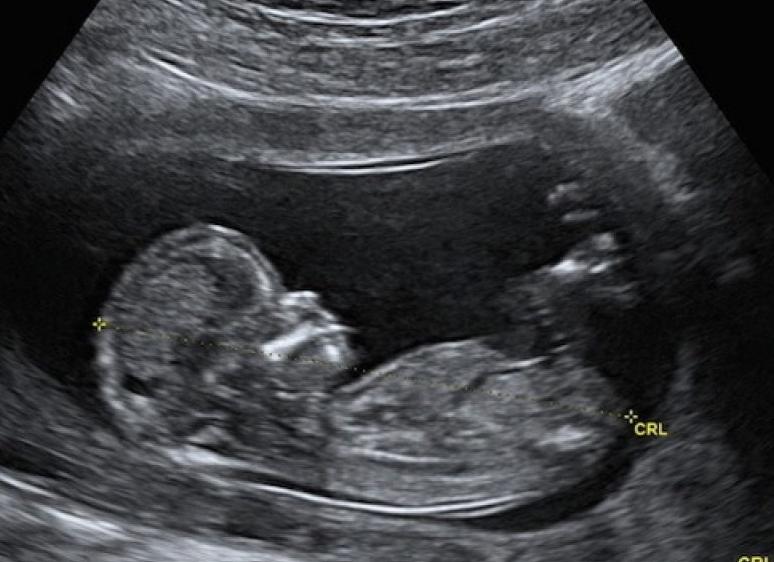

УЗИ в 12 недель

Назначается гинекологом. Проводится в пределах клиники специалистами от 11 до 13 недель. Для определения патологий и нарушений развития плода и беременности. Требуется подготовка:

В установленные сроки УЗИ показывает возможный генетический риск рождения больного ребенка. Обязательно дальнейшее изучение проблемы. Первые недели вынашивания ребенка очень важны. Норма следующих значений должна быть обозначена в результатах:

• величина эмбриона. Проводится измерение от головы и до копчика. Показатель КТР;

• расстояние от виска до виска. Данные БПР;

• толщина, плотность воротникового пространства, ТВП;

• вычисление сердечных сокращений и их частота, ЧСС.

Узнать пол ребенка посредством УЗИ на 12 неделе мечтают все будущие родители. Но определить точно это нельзя. Слишком часты ошибки со стороны врачей. Лучше в этом случае провести УЗИ на 16 неделе развития плода.

Ультразвуковое исследование на 12-й неделе беременности имеет особое значение в жизни и малыша, и будущей мамы. На этом сроке впервые можно увидеть ребенка целиком, оценить анатомическое строение плода, выявить наличие/отсутствие серьезных пороков развития. Расшифровка результатов УЗИ в этот период очень важна для определения дальнейшей тактики ведения беременности и сохранения жизнедеятельности младенца.

Что показывает ультразвуковое сканирование?

Скрининг на 12 неделе вынашивания малыша имеет несколько важнейших задач. Это уточнение срока беременности, количества плодов, их размеров, частоты сердцебиения и др. При проведении УЗИ и подготовке заключения врачи смотрят и оценивают следующие параметры:

• размеры младенца (длина тела, размер головки, длина костей);

• симметричность мозговых полушарий;

• месторасположение сердечка, желудка, почек, др. органов;

• возможные пороки сердца;

• структура головного мозга;

• симптомы возможных генетических нарушений (синдромы Дауна, Эдвардса и др.);

• место, где плод прикреплен к плаценте (норма – передняя или задняя стенка матки);

• состояние пуповины (признак нормы – наличие 2 артерий и одной вены);

• показатели шейки и стенок матки (шейка матки не должна превышать в длину 30 мм);

• конкретный срок беременности.

В преддверии второго триместра будущая мама направляется на всевозможные диагностические обследования.УЗИ на 12 неделе беременности проводится планово. С помощью исследования определяют размер плода и определяют дату родов. Следует помнить, что УЗИ свойственно ошибаться на 1 неделю, поэтому дату родов рассматривают как приблизительную. Мама впервые увидит плод крошечным человечком.